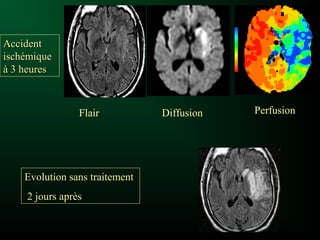

Accident

ischémique

à 3 heures

Flair Diffusion Perfusion

AccidentAccident

ischémiqueischémique

à 3 heuresà 3 heures

Evolution sans traitementEvolution sans traitement

2 jours après2 jours après